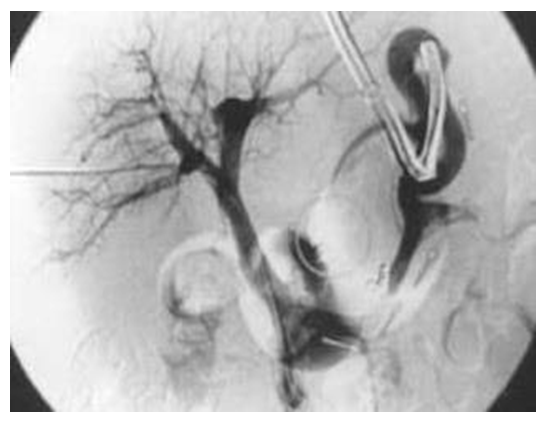

All patients in the intervention group then underwent the modified disconnection procedure as described above. Intraoperative completion portography (selective mesenteric angiography) confirmed effective interruption of the gastroesophageal venous plexus: variceal collaterals were no longer opacified after ligation of the gastric inflow (Figure 3). (Figure 3 – portogram after surgery – from control portography in dissertation【4†L101-104】 – demonstrates the clinical effect of complete disconnection: gastric varices are collapsed and not filling.) | Figure 3. Portal venography after gastroesophageal disconnection. (Postoperative “control portography” shows no filling of esophageal-gastric varices [arrow], indicating complete interruption of the gastroesophageal venous flow. Compare to baseline angiograms.) |